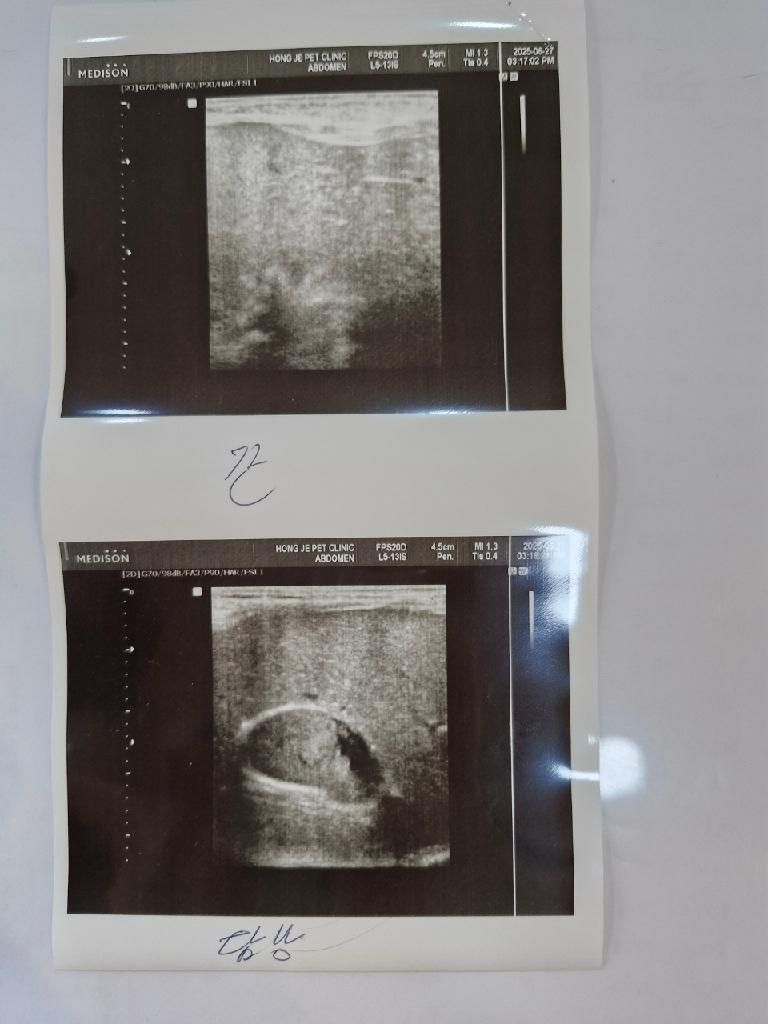

강아지 담낭.. 우루사 먹여도 될까요?

현재 d 병원에서 80퍼센트 이상정도 찬거같은데 우루사를 안주실라고했으나 제가 우루사 처방을 d 병원에서 받은 상태이고 초음파도 혈액검사도 모두 여기서 본 그런 상황입니다

강아지 담낭좀 한번 봐주시면 감사하겠습니다 우루사를 먹여도 될 수준인지 봐주세요

간 (Liver) 및 담낭 (Gallbladder) 관련 수치

GOT-PS (AST): 28 U/L (정상 범위: 17 - 44 U/L) - 정상

GPT-PS (ALT): 59 U/L (정상 범위: 17 - 78 U/L) - 정상

ALP-PS (알칼리성 인산분해효소): 174 U/L (정상 범위: 47 - 254 U/L) - 정상

TBIL-PS (총 빌리루빈): 0.2 mg/dL (정상 범위: 0.1 - 0.5 mg/dL) - 정상

ALB-PS (알부민): 4.3 g/dL (정상 범위: 2.6 - 4.0 g/dL) - 높음 (H)

TCHO-PS (총 콜레스테롤): 311 mg/dL (정상 범위: 111 - 312 mg/dL) - 정상

TG-PS (중성지방): 150 mg/dL (정상 범위: 30 - 133 mg/dL) - 높음 (H)

췌장 (Pancreas) 관련 수치

VAMY-PS (아밀라아제): 734 U/L (정상 범위: 200 - 1400 U/L) - 정상

VLIP-PS (리파아제): 75 U/L - 정상 입니다..

마지막으로 이런 경우라면 저정도 차있으면 우루사를 어느정도 용량을 받는게 맞는지도 궁금합니다

누구는 많이줘야한다 누구는 적게줘야한다 이것도 말도 또 달라서 대략적이라도좀 알고싶습니다 4.4kg 입니다